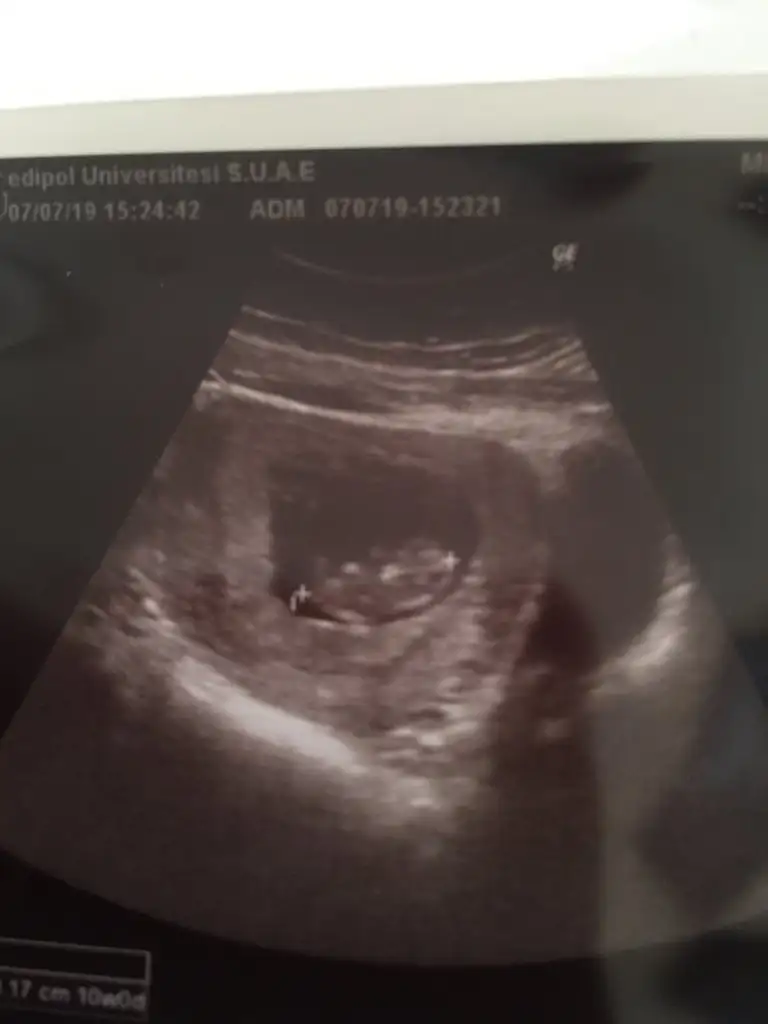

Yaaaa o zaman bende nub yorumu istiyorum 😌😌 çok uzaktan almış dr görüntüyü

😌😌 dimi canım ya bende çok merak ediyorum video çektim ama nub belli değil tam çok uzaktan görünüyo uzak almış biraz görüntüyü